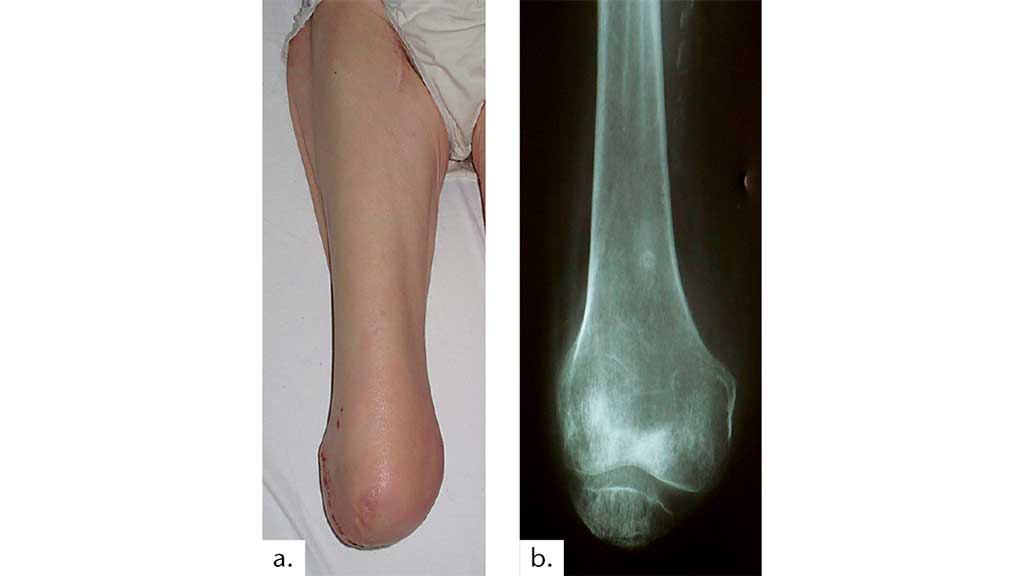

Fallvorstellung 2: ♂, 51,6 Jahre – Arbeitsunfall – Langholztransporter – Knieexartikulation, da es nicht möglich war den Unterschenkel zu erhalten – 37 Tage nach dem Unfall voll endbelastbar – 5 Monate nach dem Unfall Wiederaufnahme der beruflichen Tätigkeit (Abb. 14 a u. b).

Fallvorstellung 3: ♀, 36,6 Jahre – Suizidversuch – lange Intensiv-